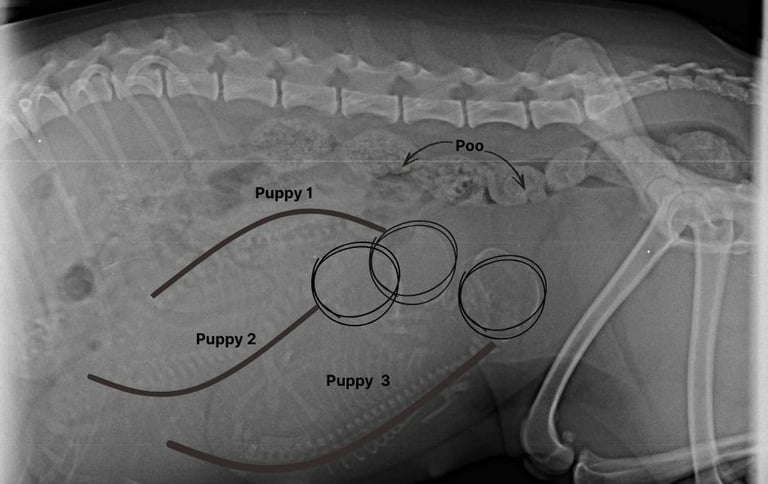

The atmosphere is carefully curated: her nest ready, blankets fluffed, room temperature kept steady, and the background tuned to “serene spa” rather than household chaos. She’s had a sanitary groom to keep her comfortable and clean, and X‑rays revealed the little lineup waiting inside—puppies poised for their grand debut, each one a secret still tucked beneath her rounded belly.

Inside the uterus, positioning becomes critical. As you can see in the x-ray, the puppies have rotated into a head‑down orientation, aligning themselves for the birth canal like actors waiting in the wings for their cue. The uterine environment is now crowded, each pup pressed against its siblings, yet still undergoing a rapid growth spurt as fat deposits accumulate to regulate body temperature after birth. Their coats are fully grown, complete with markings that will distinguish each one, and their nervous systems are firing in preparation for the sensory flood of the outside world.

Poppets X-ray. Day 56/63